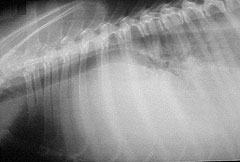

Imágenes de radiografía torácica (radiografía de tórax), e imágenes de ecocardiografía son esenciales para un diagnóstico visual preciso. Otras pruebas menos sensibles que todavía pueden proporcionar información útil acerca del corazón son la cateterización cardíaca, en la cual se inserta un tubo en una arteria o vena en el brazo o la pierna, y luego se lleva a las cámaras del corazón, y un electrocardiograma, que registra la actividad eléctrica muscular del corazón. Ambas pruebas miden la funcionalidad: la presión arterial y el flujo, el ritmo y lo bien que el músculo del corazón está bombeando.